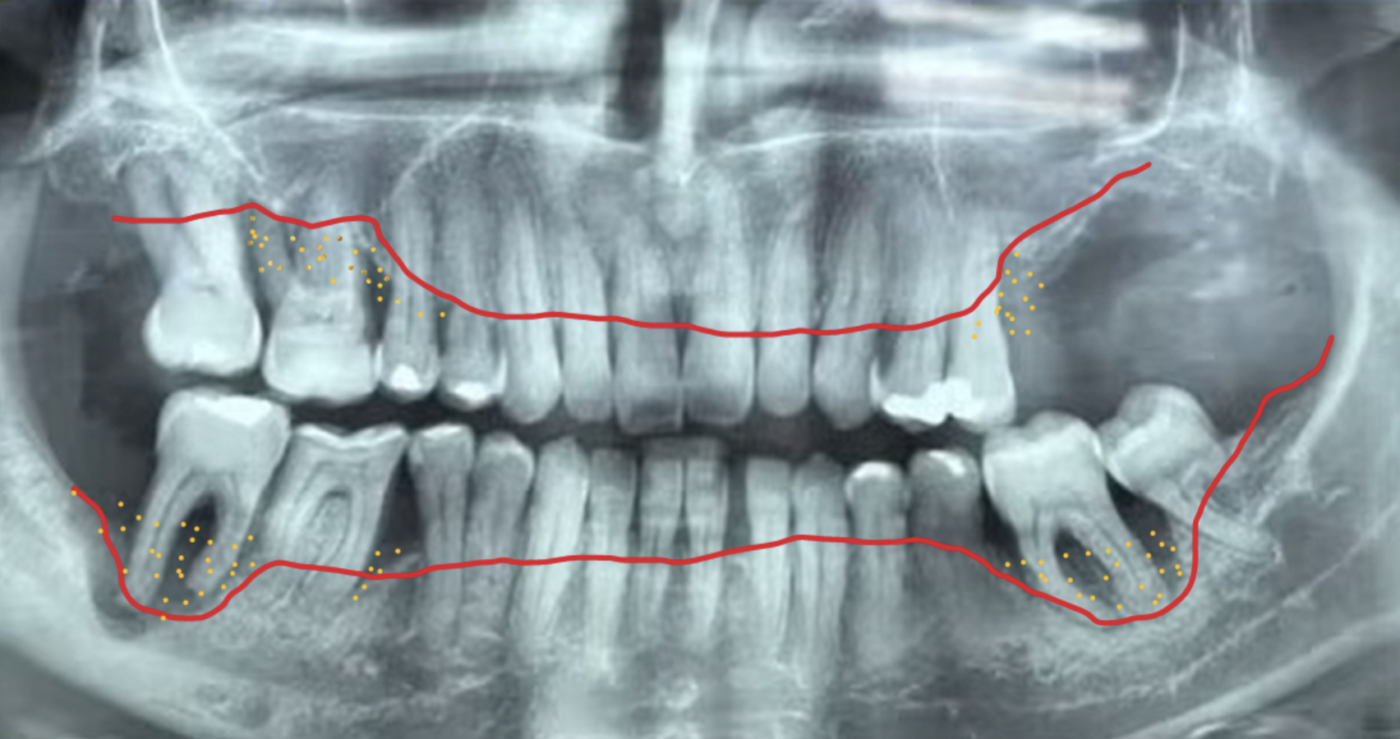

No entanto, quando esse processo inflamatório persiste ao longo do tempo sem intervenção adequada, ocorre a progressão para a periodontite. Nessa fase, o biofilme torna-se composto predominantemente por bactérias gram-negativas altamente patogênicas, capazes de induzir a destruição das fibras que ligam a gengiva ao dente, promovendo perda de inserção, reabsorção do osso de suporte e a formação das chamadas bolsas periodontais, espaços patológicos profundos onde essas bactérias se alojam e perpetuam a inflamação.

A gengiva inflamada passa então a apresentar aumento significativo de permeabilidade, permitindo a passagem direta de bactérias, endotoxinas e mediadores inflamatórios das bolsas periodontais para a corrente sanguínea, fenômeno conhecido como leaky gums, em analogia ao leaky gut intestinal. Muitas vezes silenciosa, essa condição pode evoluir sem diagnóstico precoce, manifestando-se clinicamente por halitose persistente, sangramentos espontâneos, abscessos recorrentes e, em estágios mais avançados, mobilidade dentária. Por isso, a avaliação periodontal criteriosa é fundamental: o periograma permite mapear com precisão a profundidade das bolsas periodontais, o sangramento à sondagem, a mobilidade dentária e a perda óssea, sendo uma ferramenta essencial para o diagnóstico correto e para a construção de um plano terapêutico individualizado, consciente e integrativo.

- O diagnóstico periodontal envolve exames de imagem, como radiografias e, quando necessário, tomografias, além da avaliação clínica das gengivas. Durante a consulta, são analisados sinais como sangramento gengival, mobilidade dos dentes e perda óssea. Um exame essencial nesse processo é o periograma, que mede a profundidade das bolsas periodontais ao redor de cada dente. Esse mapeamento é repetido ao longo do tratamento, permitindo acompanhar a evolução do quadro e verificar o fechamento progressivo das bolsas periodontais.